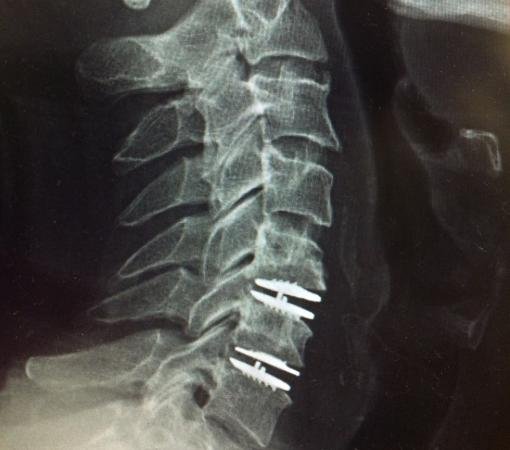

In discussions around Disc Replacement surgery in Mumbai, the team highlighted that not every patient with disc-related pain is a candidate. Careful evaluation—including imaging, neurological assessment, and response to conservative treatment—forms the backbone of decision-making. This cautious, layered approach reflects clinical maturity rather than procedural enthusiasm.